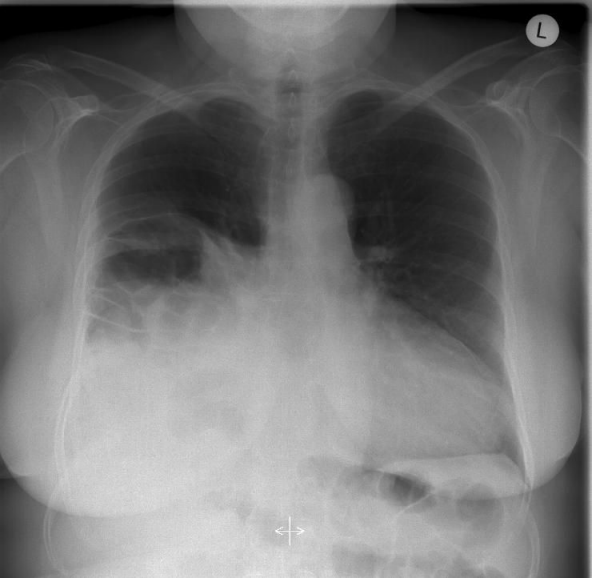

Accuracy of chest X-ray has been described as high as 62% for left-sided but only 17% for right-sided injuries [11]. In our study chest X-ray (Figure 1 [Fig. 1]) showed diaphragmatic hernia in 4 of 7 patients (57%). Abdominal/pleural ultrasound seems to have an even lower accuracy in detecting diaphragmatic rupture. Accuracy was 0% to 26% in various studies [10], [12]. In our series in only one of four patients ultrasound was suspicious for diaphragmatic injury.

Figure 1: Thoracal X-ray of a patient with right-sided diaphragmatic rupture